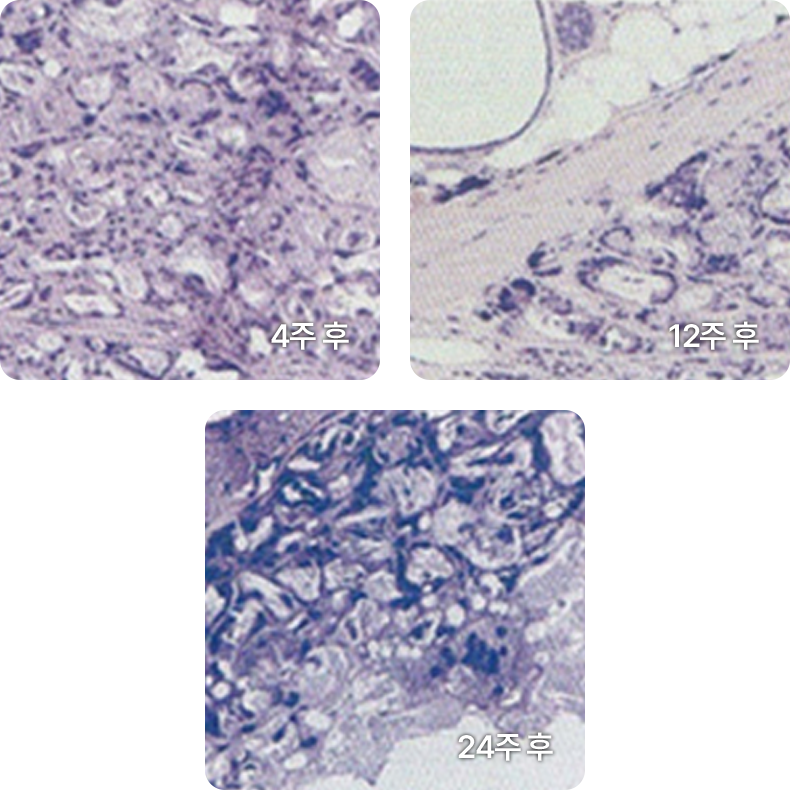

콜라겐 재생이 촉진되어 차오르는 것을 확인할 수 있습니다.

콜라겐 밀도 증가